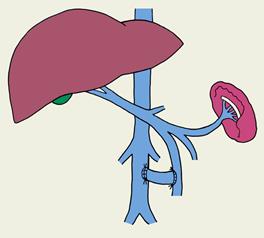

В нашей стране получила распространение операция деваскуляризации, разработанная М.Д. Пациорой (1974). Сущность ее состоит в прошивании и перевязке отдельными лигатурами варикозных вен кардиального отдела желудка и пищевода со стороны слизистой оболочки, перевязке венечной вены желудка и левых желудочных сосудов, иногда в сочетании со спленэктомией (рис. 4). Операцию выполняют из абдоминального доступа, она менее травматична и технически проста. Существенным недостатком данной методики является неполное разобщение интрамуральных вен желудка и пищевода. Мелкие вены гастроэзофагеальной сети анастомозов остаются неперевязанными, сброс крови по ним продолжается и даже увеличивается. Таким образом сохраняются условия для рецидива варикозного расширения вен и пищеводных кровотечений.

Рис. 4. Операция Пациоры.

Достаточно полное интрамуральных венозных сетей пищевода и желудка достигается при трансторакальной субмукозной транссекции пищевода по Walker (1982). Однако и эта операция нередко дает рецидивы и осложнения.